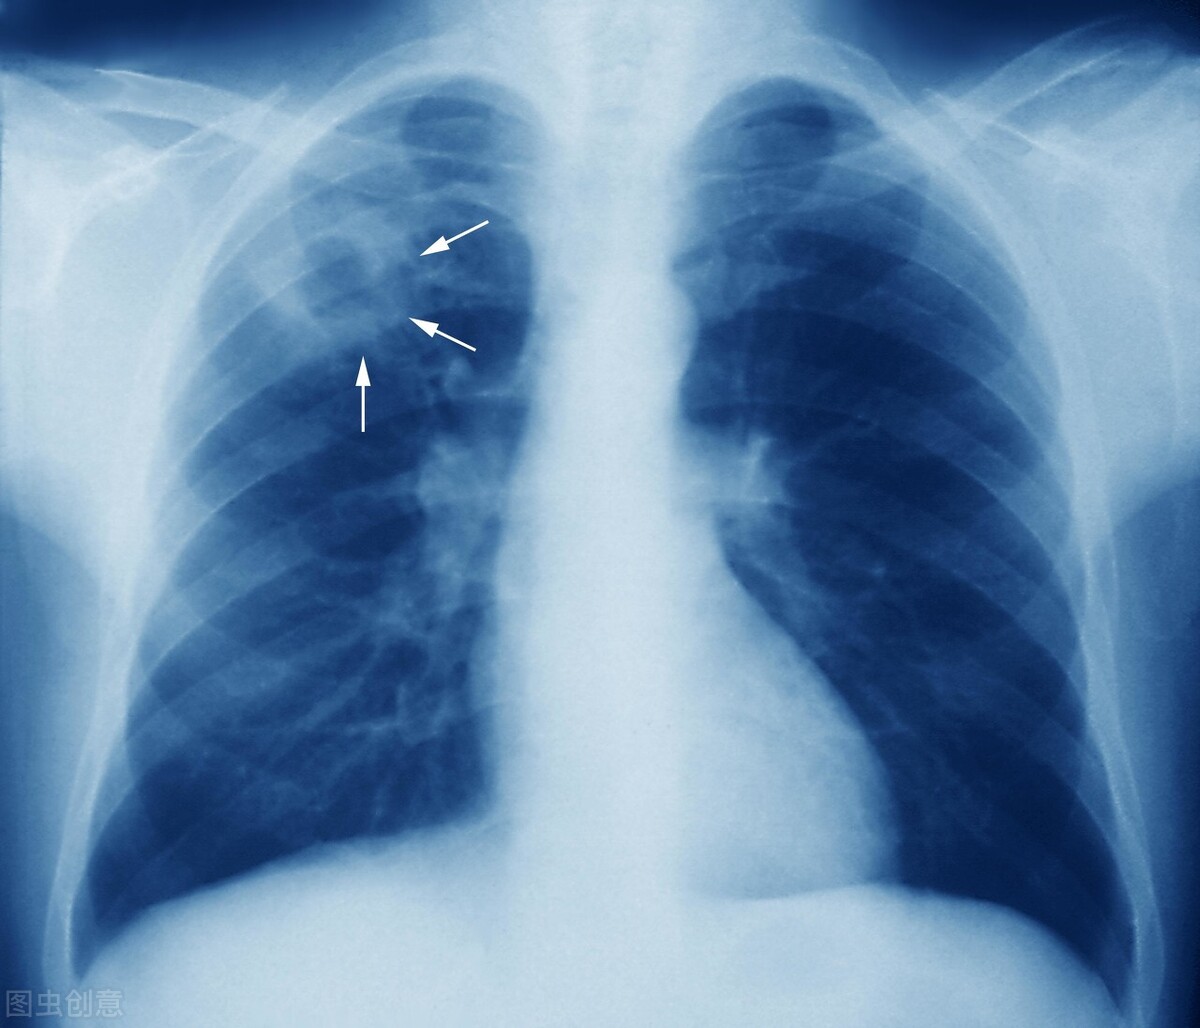

肺结节作为一种常见的肺部问题,要重视起来,久而久之疾病也可能恶化,尤其是具有边缘不清晰,有分叶、毛刺、空泡、凹陷以及血管穿行等特征的结节,以及混合结节,都是有较高恶变几率的,要及早调治,莫因为忽视而延误病情。